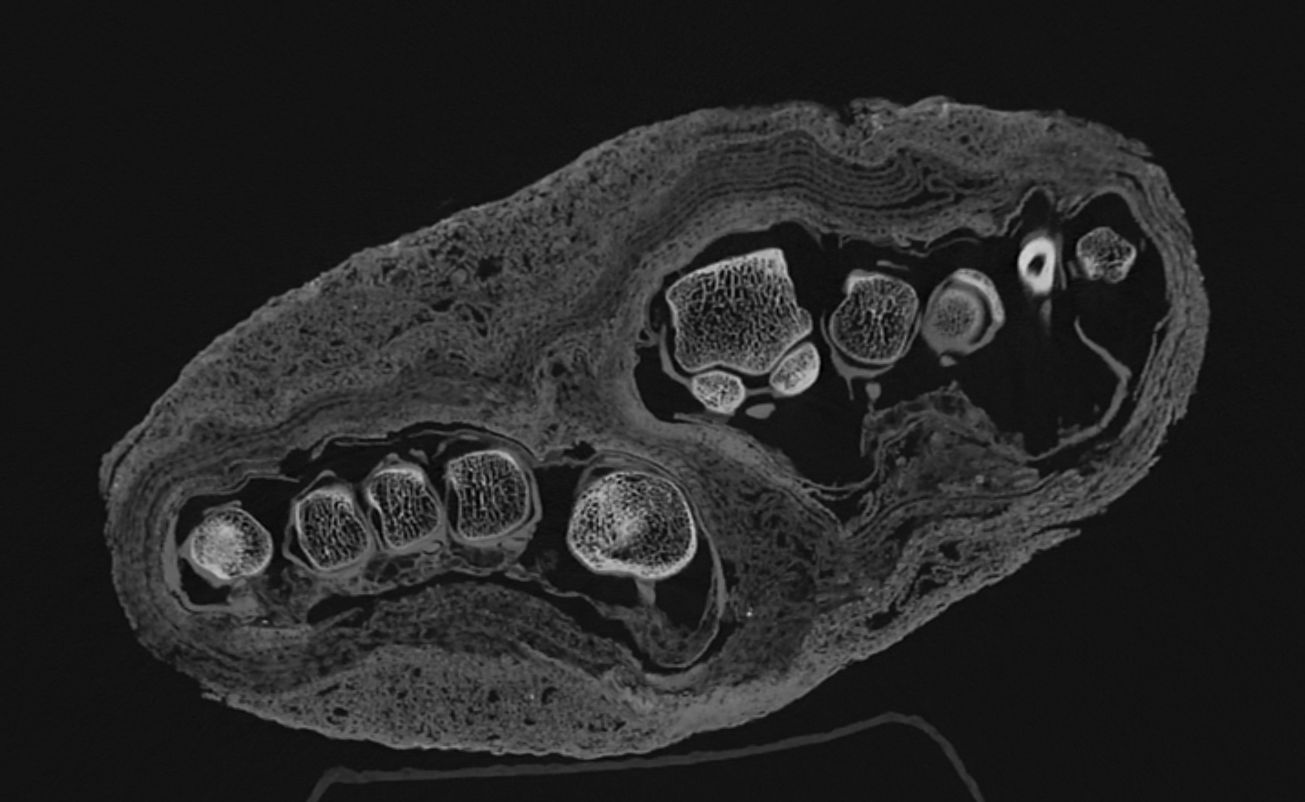

The recent high-resolution CT scans allow for a more detailed examination of the teeth and skull sutures of the two mummified heads. This could lead to a more accurate age determination and lay the groundwork for future high-precision, detailed 3D reconstructions, as well as potential facial reconstructions of the skulls.

The examination of a set of remains – previously interpreted merely as a mummy bundle – yielded particularly noteworthy results. When the find arrived at the museum, in the absence of imaging tests, it was initially identified as a human head and later, possibly, as a bird mummy. However, a previous CT scan clearly showed that the find is, in fact, an adult foot. The current imaging analysis aims to determine the extent to which the textile remnants can provide insight into the mummification technique, the age of the mummified individual, and any illnesses the individual may have had. The current images clearly reveal the different layers of the bandage and show their different structural characteristics. These findings may lay the groundwork for further historical and technological investigations. The remains were presumably part of a complete mummy, but the reason and time of the dissection are currently unknown.